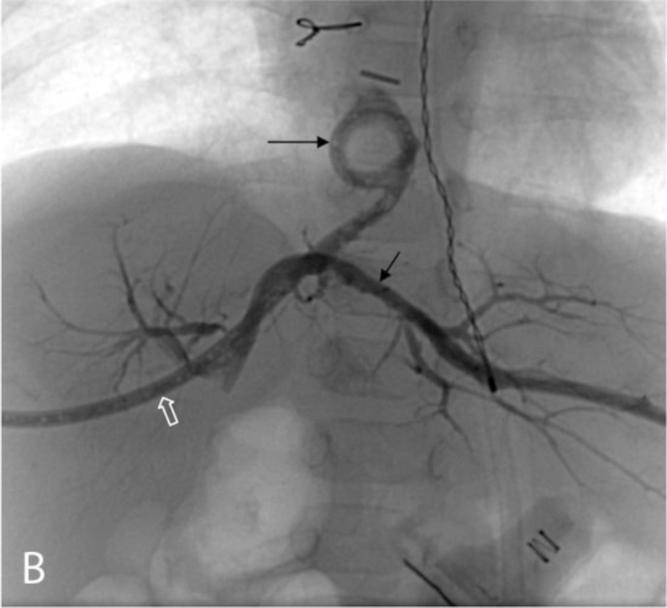

Congenital tracheobiliary or bronchobiliary fistula is a rare developmental anomaly with a persistent communication between the biliary system and the trachea or bronchus. We report a case of a congenital tracheobiliary fistula and hypoplastic common hepatic duct associated with hypoplastic left heart syndrome in a 5-day old boy presenting with bilious endotracheal-tube secretions. The tracheobiliary fistula was treated by surgical resection. Subsequent cholangiography demonstrated dilated intrahepatic bile ducts and a residual fistulous tract with cystic proximal stump that were successfully decompressed by transhepatic drainage catheters before corrective biliary surgery.

先天性气管胆管或支气管胆管瘘是一种罕见的发育异常,其特征为胆道系统与气管或支气管之间存在持续的连通。我们报告了一例5日龄男婴,患有先天性气管胆管瘘、肝总管发育不全并伴有左心发育不全综合征,该患儿出现胆汁性气管插管分泌物。通过手术切除治疗气管胆管瘘。随后的胆管造影显示肝内胆管扩张以及存在残余瘘管,其近端呈囊性残端,在进行矫正性胆道手术前,经肝引流导管成功对其进行了减压。